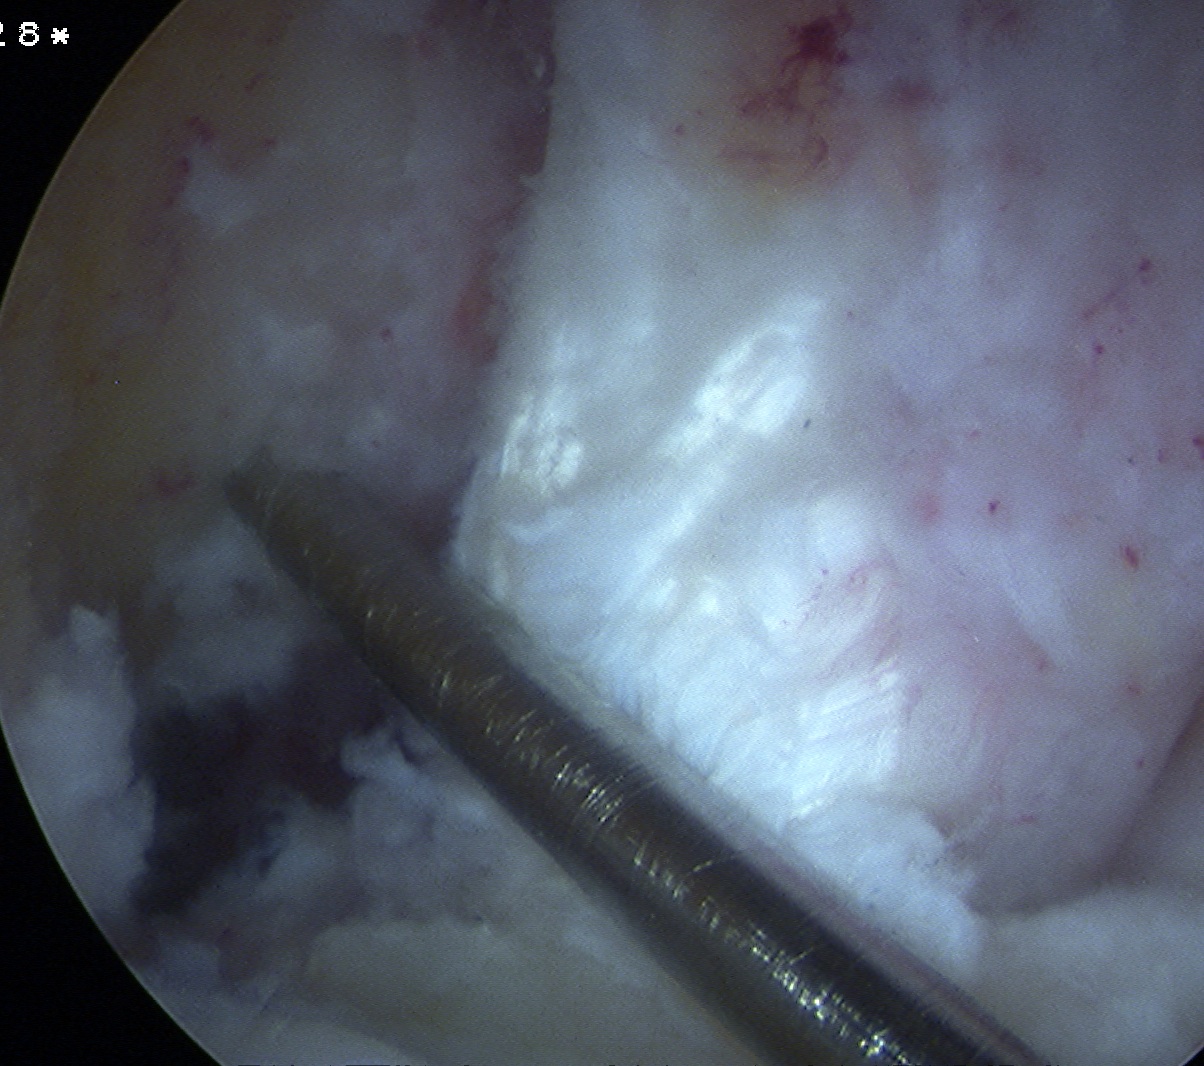

Debride ACL

Debride stump back to PCL fibres (preserve synovium over PCL)

- can leave some stump to identify tibial tunnel and provide vascularisation

- clean lateral wall

- remove periosteum with curette, chondrotome and electrocautery

- identify resident's ridge and posterior wall clearly